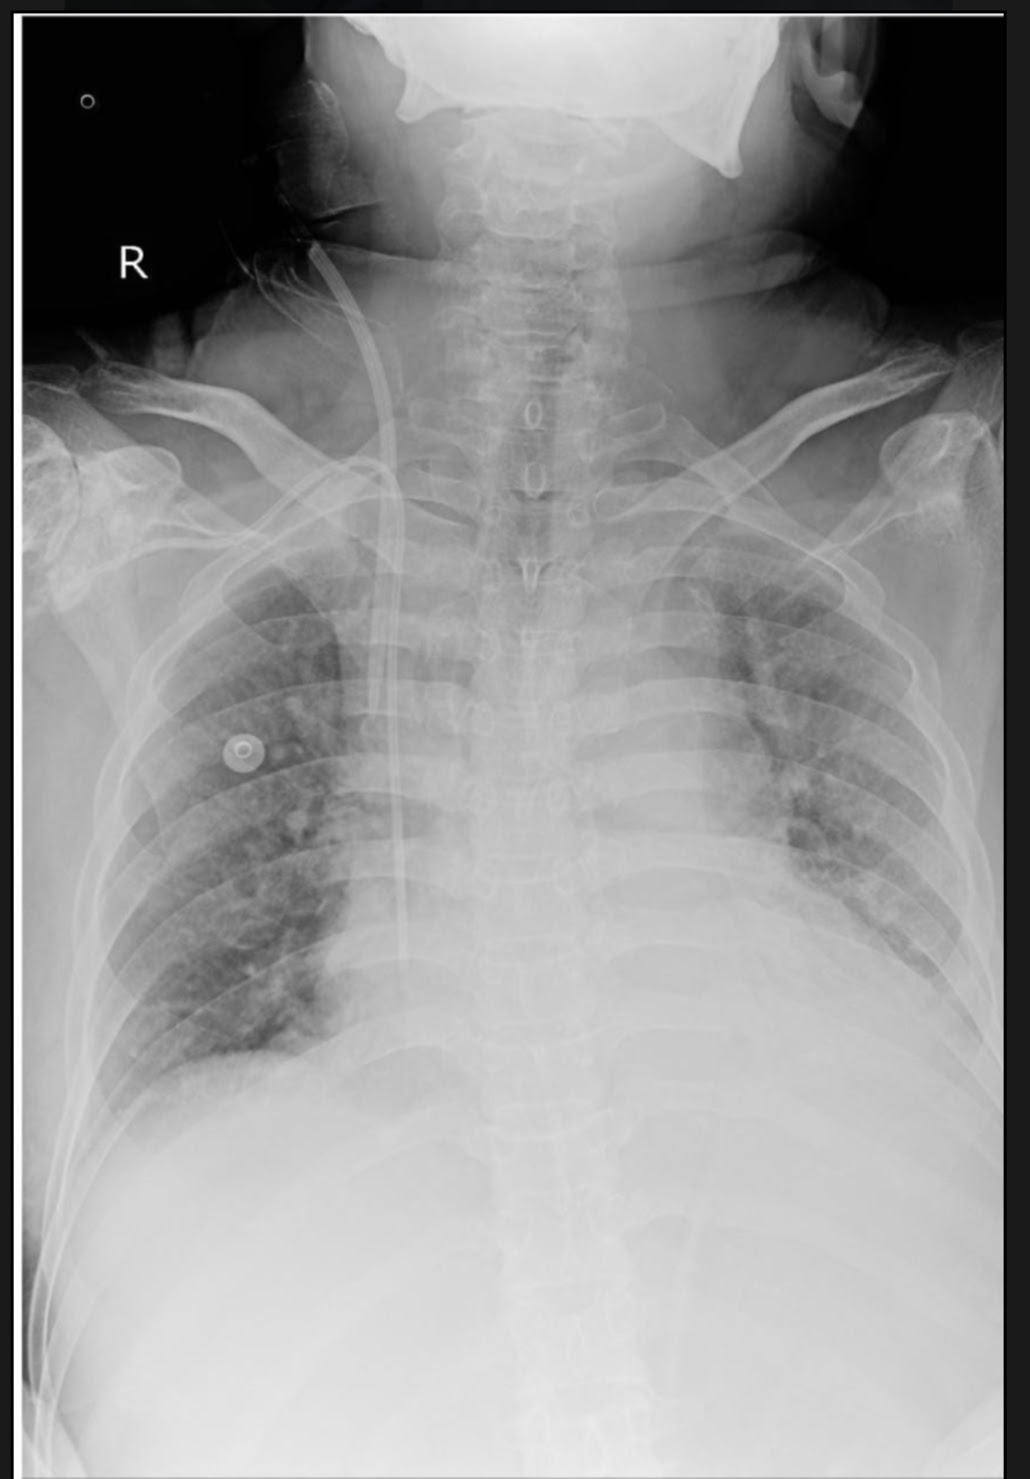

A 55 years male patient from kondapakagudem ,presented to OPD on 04.08.2021 with a complaint of decreased urine output since 3 days.

-Patient was apparently asymtomatic till 1997 when he had fallen from the current pole after which he had injury to the left upperlimb,lowerlimb and lower back for which he had started using painkillers since many years ,till 1 month back.

-6 years back he started developing pedal edema in both limbs which is pitting type extending upto both the knees.

-6 years back he also developed knee joint pains and swelling.

-Patient had a trauma 1month back at right lower limb at the ankle due to bike accident,which got infected and medicated with some antibiotics. The wound didnot subside even after taking antibiotics.

-15 days ago he developed shortness of breathing for which he was taken to the hospital and there he was supplied with oxygen for his shortness of breathing. There the doctors told him that his serum creatinine levels are elevated and advised him dialysis.

-While the patient is being prepared for cvp line he suffered from cardiac arrest and was resescitated.

-On first day of dialysis doctors collected fluid from his both knees.

-From then he undergone dialysis for 6 times after his 6th dialysis patient was taken home.

-After going home patient developed decreased urine output and for this reason he brought to our casuality.

General Examination:-

Patient is conscious,coherent and cooperative.

No signs of pallor ,icterus,synosis and lymphadenopathy.

Clubbing is present

Edema is present in both the lower limbs which is pitting type extending upto both the knees.Vitals:-